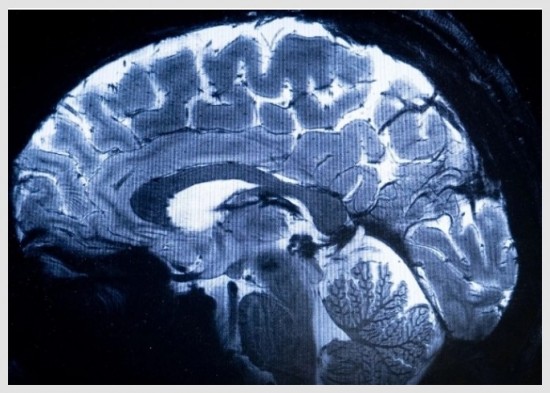

Distintos estudios en neurociencia demostraron que el lóbulo frontal es la parte del cerebro que se encarga de la toma de decisiones, este reúne datos del entorno para dirigir una conducta basada en el razonamiento. La suposición de tener todo el contenido, los investigadores lo llamaron la ilusión de adecuación de la información.